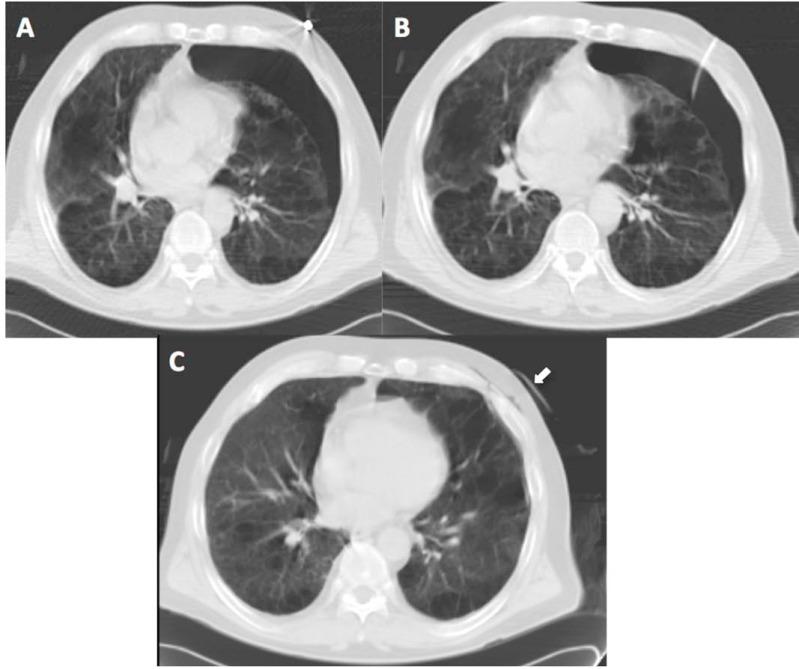

Percutanous needle biopsy of the lung (PNBL), under image guidance, has established itself as a safe and effective minimally-invasive method of obtaining a tissue diagnosis of pulmonary lesions, for selected patients with suspected pathologic processes. The purpose of this study was to evaluate the diagnostic yield and safety of percutaneous core biopsy of the lung (PCBL) without Fine Needle Aspiration Biopsy (FNAB), with specific attention to potential risk factors that may predict post-biopsy pneumothorax.

A retrospective analysis of 75 consecutive PCBL procedures between January 2006 to March 2008 involving 72 patients with a documented pulmonary nodule or mass lesion on CT scan of Thorax. The study population included 38 males (52.8%) and 34 females (47.2%) aged 20-85 years (mean age 63.6 years). A co-axial cutting system with a 19-gauge outer needle and a 20-gauge inner automated cutting needle (Temno, Allegiance Healthcare Corporation, Ohio, USA) was used in all patients.

Lesions varied in size from 0.7cm to 10.7cm (mean maximum trans-axial diameter 3.1cm). The mean number of core biopsy samples obtained was 3.1 (range 1-5). Of the 75 PCBL procedures, 71 yielded specimens adequate for histopathologic evaluation, consistent with a technical success rate of 95%. Malignancy was detected in 48 specimens (64%) and benign diagnoses were identified in 23 specimens (31%). As mentioned, 4 specimens (5%) were nondiagnostic. The most common biopsy-induced complication was pneumothorax, occurring in 15 patients (20%), with 4 (5.3%) requiring thoracostomy tube placement.

在影像引导下,经皮肺穿刺活检(PNBL)已成为一种安全有效的微创方法,可为选定的疑似病理过程患者获取肺部病变的组织诊断。本研究的目的是评估不进行细针穿刺抽吸活检(FNAB)的经皮肺芯针活检(PCBL)的诊断率和安全性,特别关注可能预测活检后气胸的潜在危险因素。

对2006年1月至2008年3月期间连续进行的75例PCBL手术进行回顾性分析,这些手术涉及72例经胸部CT扫描记录有肺结节或肿块病变的患者。研究人群包括38名男性(52.8%)和34名女性(47.2%),年龄在20 - 85岁之间(平均年龄63.6岁)。所有患者均使用带有19号外针和20号内自动切割针的同轴切割系统(Temno,美国俄亥俄州忠诚医疗保健公司)。

病变大小从0.7厘米至10.7厘米不等(平均最大横轴直径3.1厘米)。获得的芯针活检样本平均数量为3.1个(范围为1 - 5个)。在75例PCBL手术中,71例获得了足以进行组织病理学评估的标本,技术成功率为95%。48例标本(64%)检测到恶性肿瘤,23例标本(31%)确定为良性诊断。如前所述,4例标本(5%)无法诊断。最常见的活检引起的并发症是气胸,15例患者(20%)发生气胸,其中4例(5.3%)需要放置胸腔引流管。